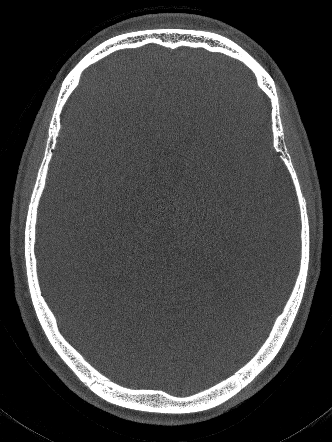

We use Adam optimization with learning rate of 0.000010.000010.00001 and select the network parameters that achieved the best RPE prediction on our validation dataset. Our network achieves an average RPE deviation from the Gt of 0.0310.0310.031 mm on the test dataset, as depicted in Fig. 1.

Figure 1: Network estimated RPE and different reconstructions, all revealing a RPE of 0.34absent0.34\approx 0.34 mm.